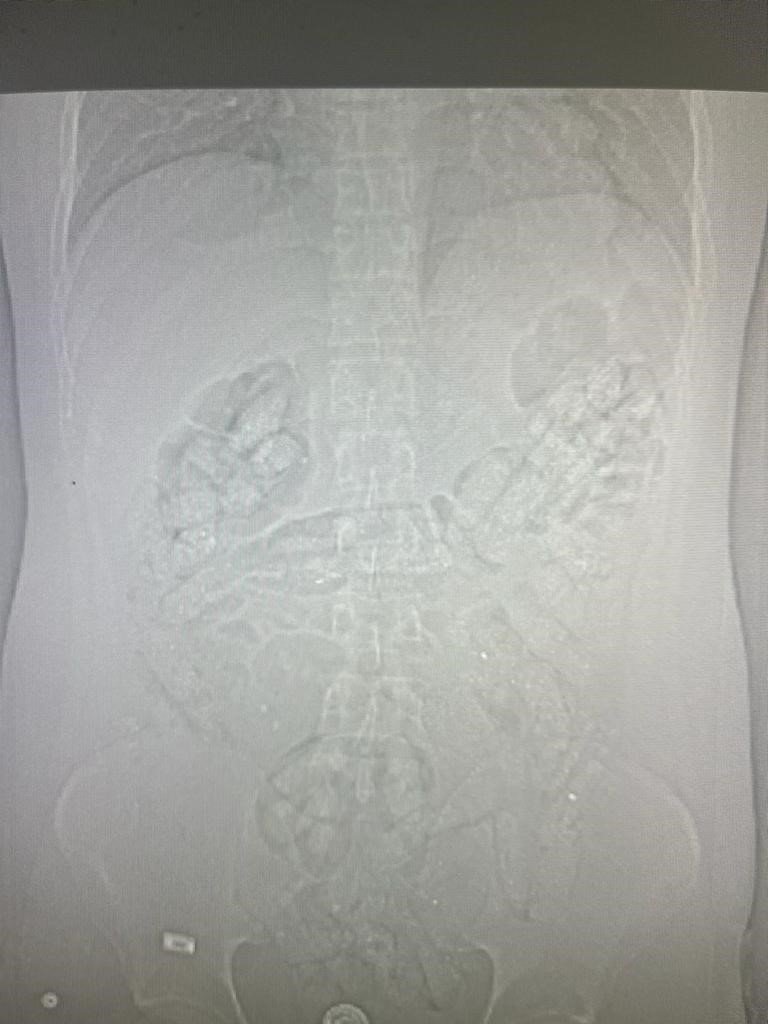

Erzincan İl Emniyet Müdürlüğü Narkotik Suçlarla Mücadele Şube Müdürlüğü ekiplerince uyuşturucu madde kuryeliği yapan şahıslara yönelik İran otobüsleri üzerinde yapılan uygulamada; İran otobüsünde yolculuk yapan Abdulmennan S. isimli İran uyruklu kişinin yutma yöntemiyle uyuşturucu taşıdığı değerlendirilmesi üzerine, Erzincan Mengücek Gazi Eğitim ve Araştırma Hastanesinde zanlının bedeninden 106 fişek halinde toplamda 1 kilo 198 gram Afyon Sakızı ele geçirildi. Abdulmennan S. hakkında TCK 188 suçundan yapılan tahkikat sonrası sevk edildiği mahkemece tutuklanarak cezaevine teslim gönderildi.